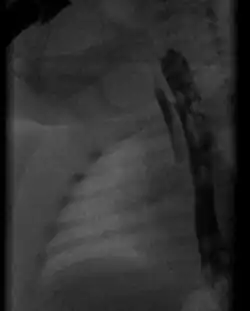

Radiograph with oral contrast showing h-type tracheoesophageal fistula in a newborn

Type E (or H-Type) - A variant of type D: if the two segments of esophagus communicate, this is sometimes termed an H-type fistula due to its resemblance to the letter H. TEF without EA. No Yes